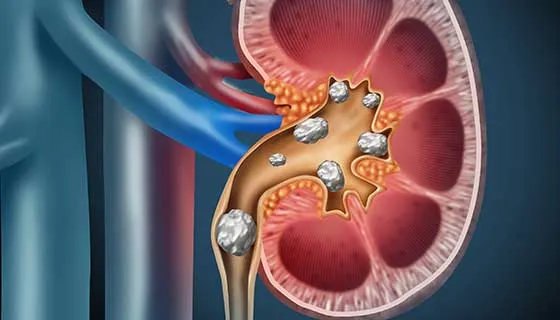

Doação renal em mulheres jovens pode impactar mais o feto do que a mãe — e esse dado muda o pré-operatório. O maior estudo já feito mostra aumento de PIG e sinais de disfunção placentária silenciosa, especialmente em nulíparas. Se você ainda não discute isso de forma explícita no consentimento, talvez esteja subestimando o risco.